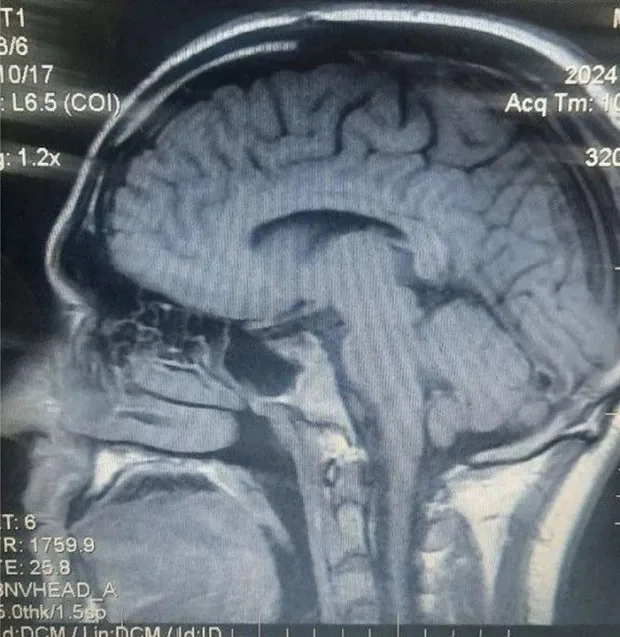

뇌척수액(Cerebrospinal Fluid, CSF)은 뇌와 척수를 둘러싸고 있는 투명한 액체로, 신경계를 보호하고 다양한 생리적 기능을 수행하는 중요한 물질입니다. 이 글에서는 뇌척수액의 생성, 구성, 순환 경로, 기능, 그리고 의학적 활용까지 종합적으로 설명합니다.

생성 장소: 주로 뇌실(ventricles) 내부에 있는 맥락총(choroid plexus)이라는 특수 조직에서 생성됩니다. 맥락총은 혈관과 신경 세포로 이루어진 구조로, 혈장 성분을 걸러내어 뇌척수액을 만듭니다.

순환 경로: 뇌실에서 생성된 뇌척수액은 중심뇌수조(제3·4뇌실) → 측뇌수조(제2뇌실) → 거미막밑공간(subarachnoid space)을 통해 뇌와 척수를 순환한 뒤, 경질막정맥굴으로 배출됩니다. 순환 속도는 분당 4~5mL 정도로 느리지만, 뇌 전체를 지속적으로 순환하며 노폐물을 제거합니다.